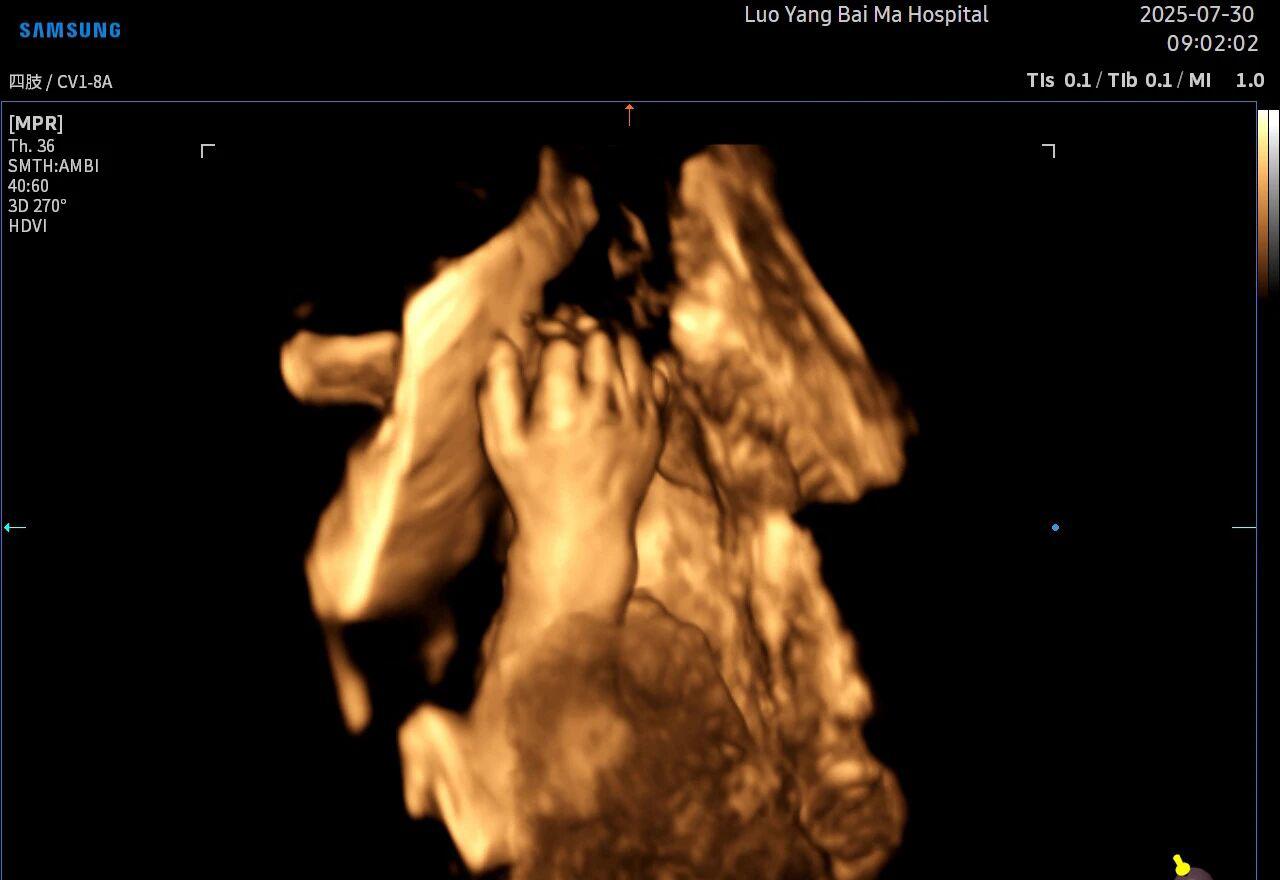

很多准妈妈可能对四维(4D)彩超已经非常熟悉,它能够实时动态地展示宝宝在宫内的活动,让我们看到宝宝打哈欠、伸懒腰的可爱模样,为无数家庭留下了珍贵的第一份“动态影集”。

5D智能彩超拥有更高的分辨率和更强的图像处理能力,能够呈现出接近“IMAX电影画质”的细腻影像 。它采用一种被称为“水晶成像”的技术,能够穿透组织,将胎儿的骨骼、器官和组织结构以极其清晰、立体的形态展示出来。这种高清晰度对于观察胎儿微小的解剖结构细节至关重要,例如手指、脚趾、耳廓形态等,有助于医生发现一些在传统超声下不易察觉的细微异常,为排畸诊断提供了更丰富的视觉信息。

传统超声检查有时会因为胎儿体位、羊水量等因素的限制,导致某些部位观察不清。5D智能彩超技术能够实现对目标结构进行360°全方位、多切面的自由旋转观察。医生可以像“雕塑家”一样,从任意角度审视胎儿的解剖结构,尤其对于形态复杂的心脏、颅脑和脊柱等部位,这种能力可以极大弥补单一平面的局限性,帮助医生更全面地评估其发育状况。